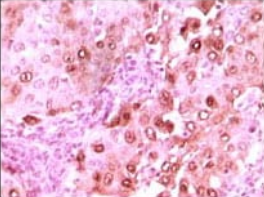

IHC    1/200 - 1/1000